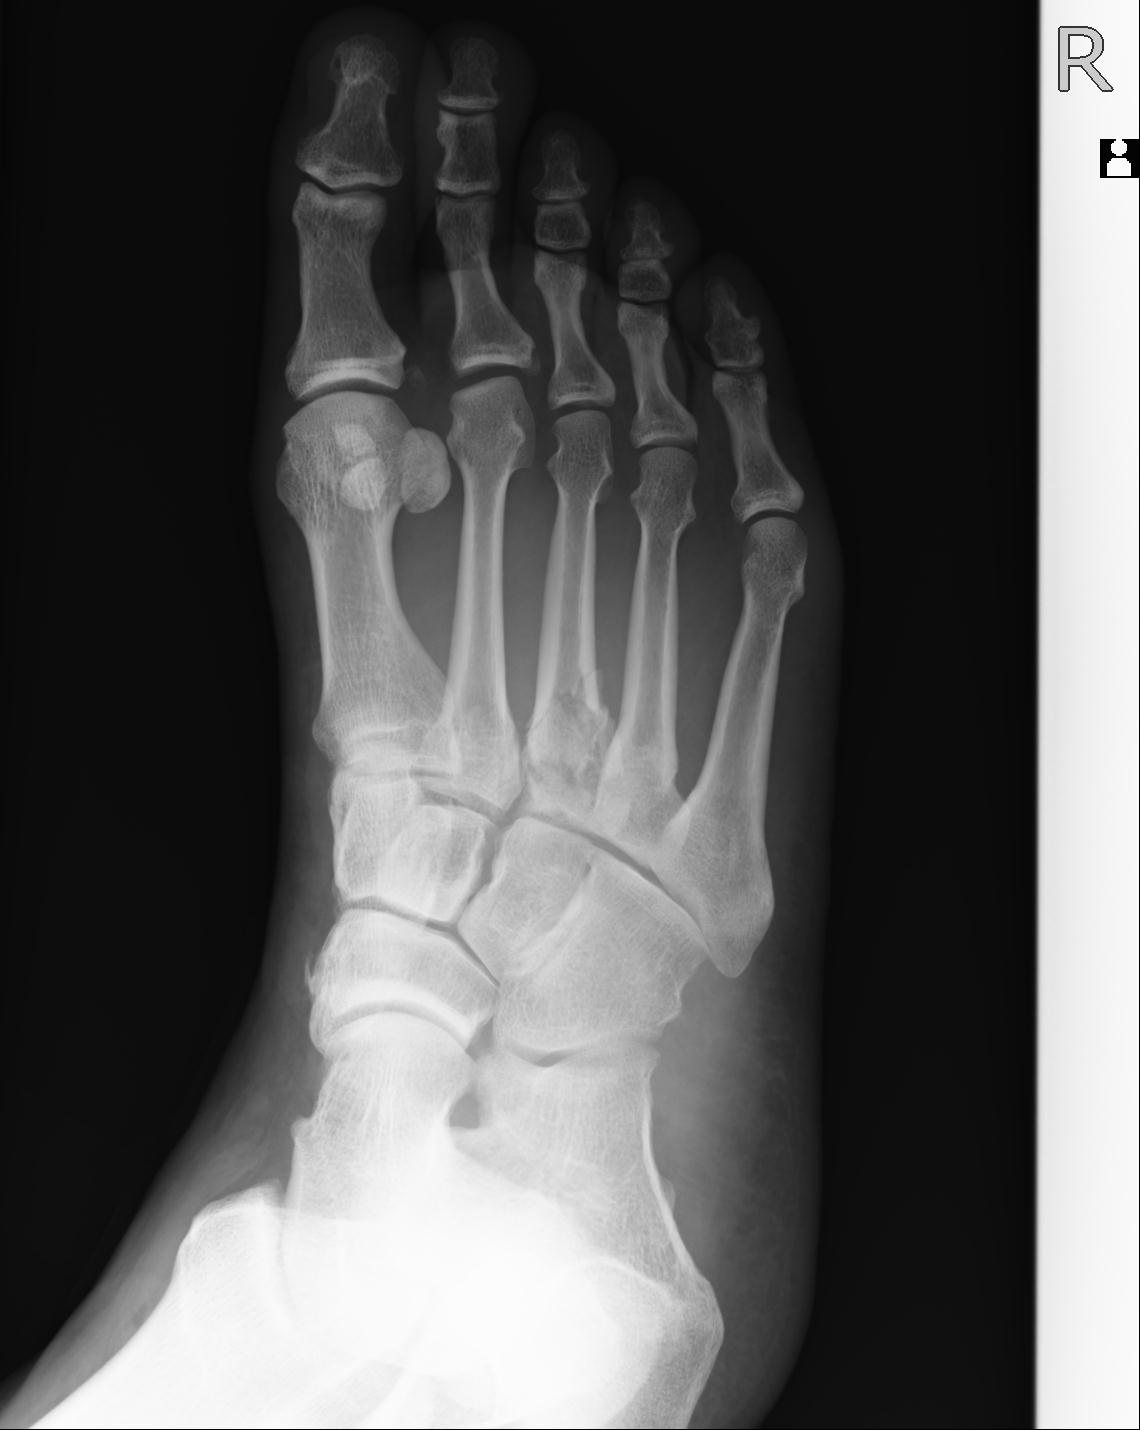

103177 3/11 右足 2R 3/16 右足 2R リスフラン脱臼 55歳男性